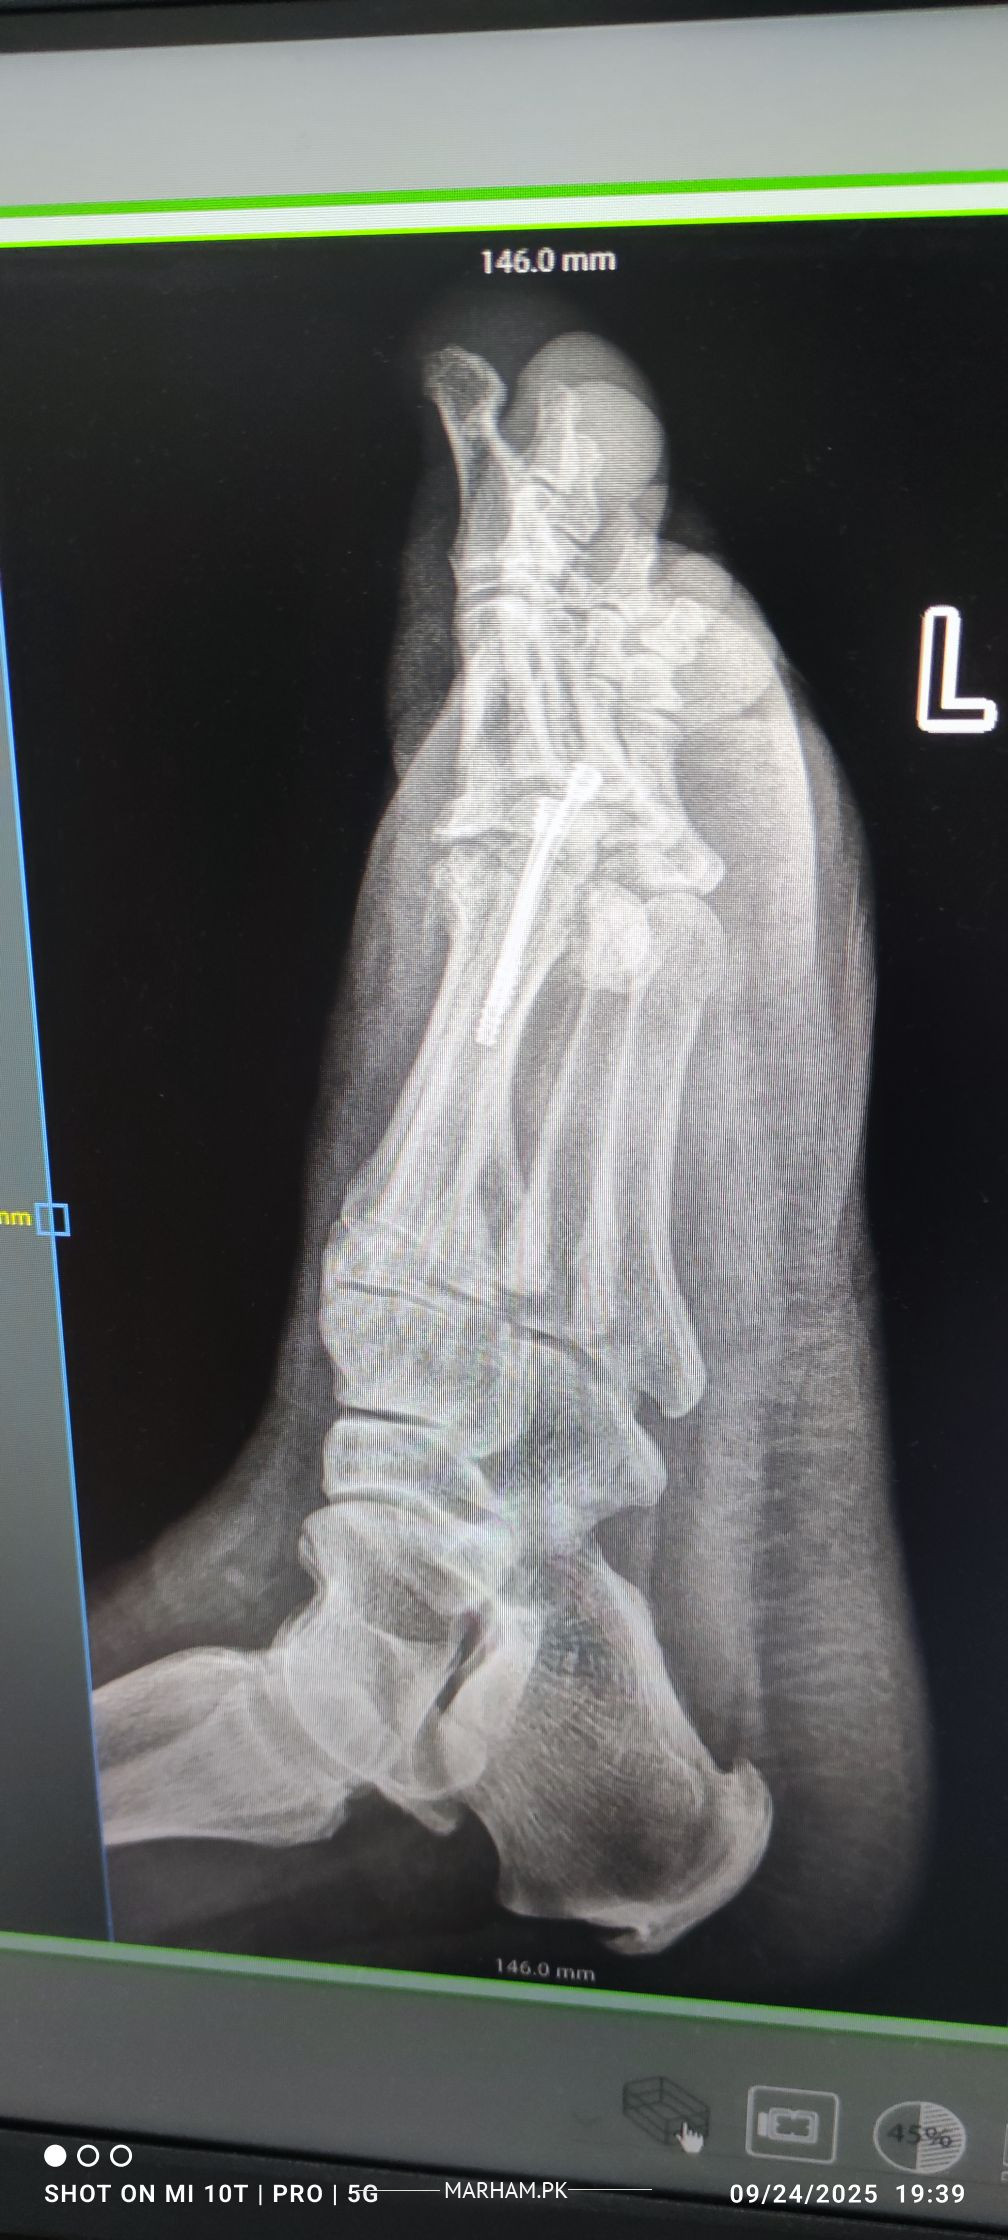

Talk to Orthopedic Surgeon on Post Operation X-ray

AoA, kindly ye meri mother ki xray report daikh kar bta dain k operation theek ho gya hai, X-ray main fracture nazar aa rha hai lekin, technician ny b kaha k fracture show ho rha hai kisi doctor ko dikha dain. shukria

Better to consult your treating surgeon again please.

Thank you

Need following informations

1- Date of injury or weeks

2- XRay before Surgery

3- XRay just after surgery

4- XRay latest , you already shared

Regards

get examined by surgeon for complete history and details regarding surgery.

Osteotomy means cutting the bone to straighten it, usually to relieve pain or improve joint function. After the cut, the bone is held in place with plates, screws or pins while it heals. Most people need a period of limited weight‑bearing followed by physical therapy to rebuild strength and range of motion. Recovery can take several months, and the goal is to return to normal activities, but some patients may still need braces or activity adjustments. The procedure is common for knee, hip or foot problems, and outcomes are generally good when the surgeon’s plan matches the patient’s anatomy and the rehab is followed closely. If you’re considering it, talk to an orthopedic surgeon about your specific condition, the expected healing time, and any lifestyle changes that will help you recover fully.